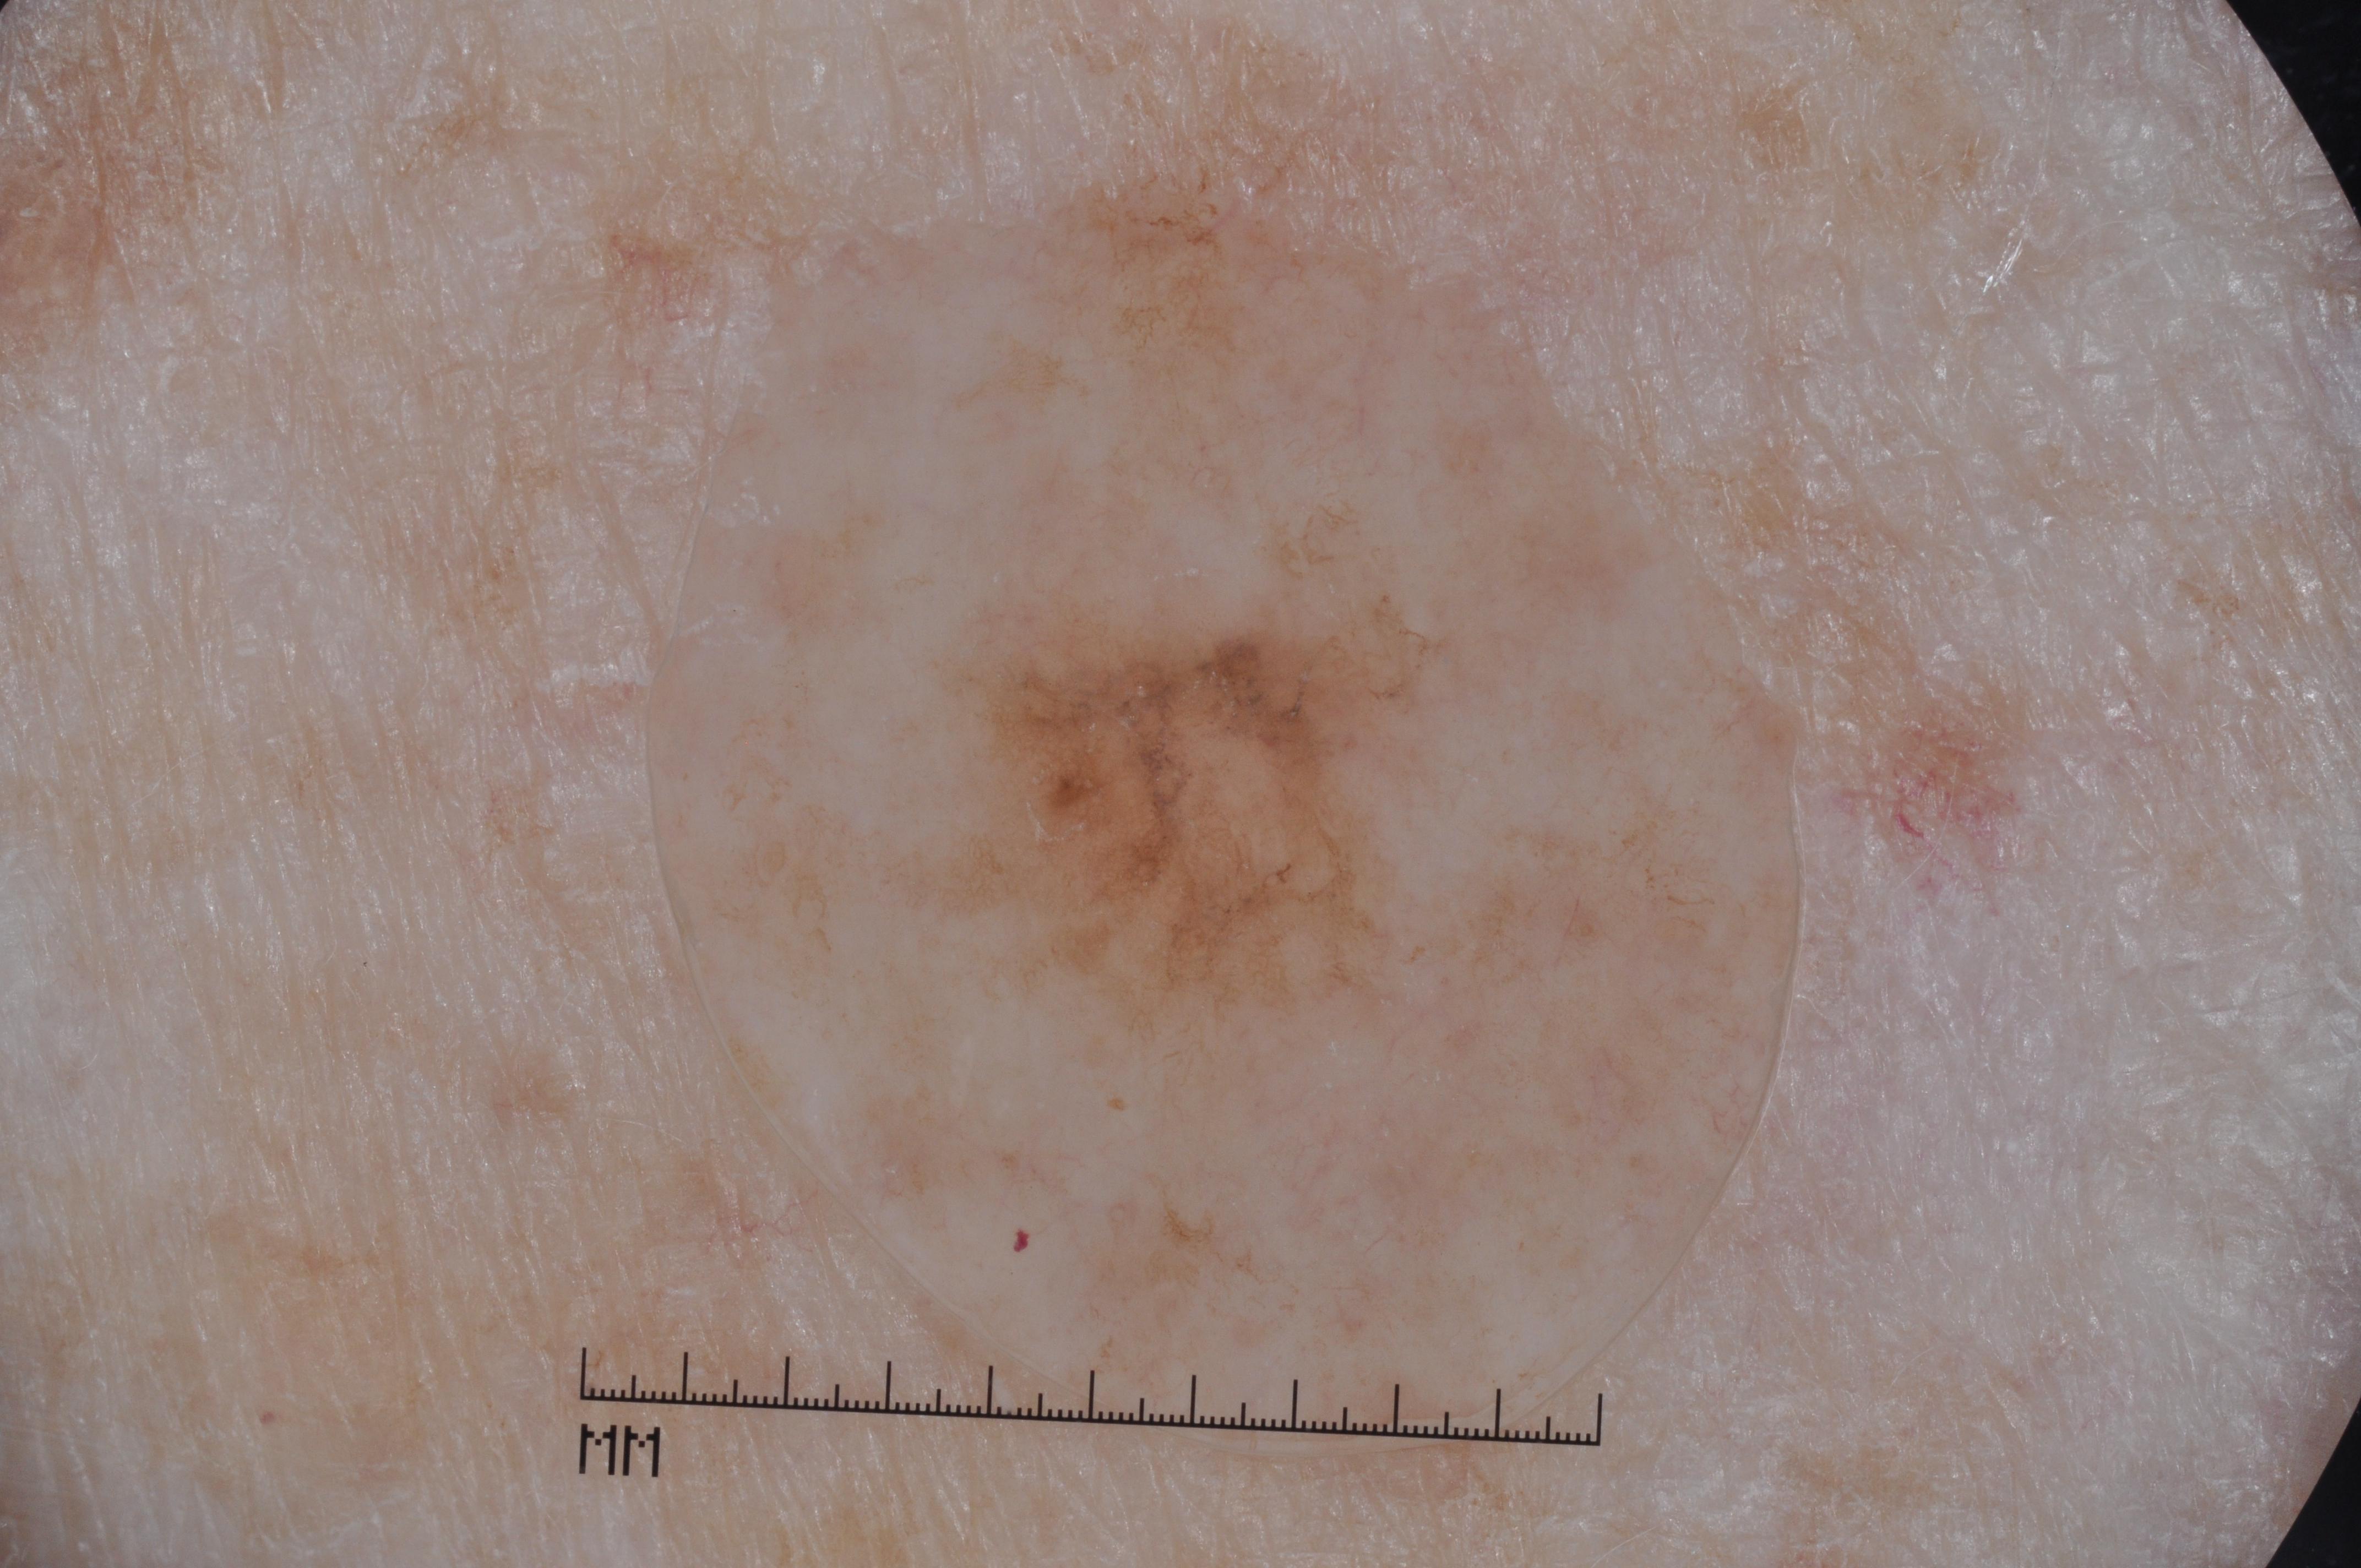

{

"acquisition_day": 1,

"age_approx": 75,

"anatom_site_general": "upper extremity",

"concomitant_biopsy": true,

"diagnosis_1": "Malignant",

"diagnosis_2": "Malignant melanocytic proliferations (Melanoma)",

"diagnosis_3": "Melanoma in situ",

"diagnosis_confirm_type": "histopathology",

"image_manipulation": "instrument only",

"image_type": "dermoscopic",

"lesion_id": "IL_1202398",

"melanocytic": true,

"patient_id": "IP_3010556",

"sex": "male"